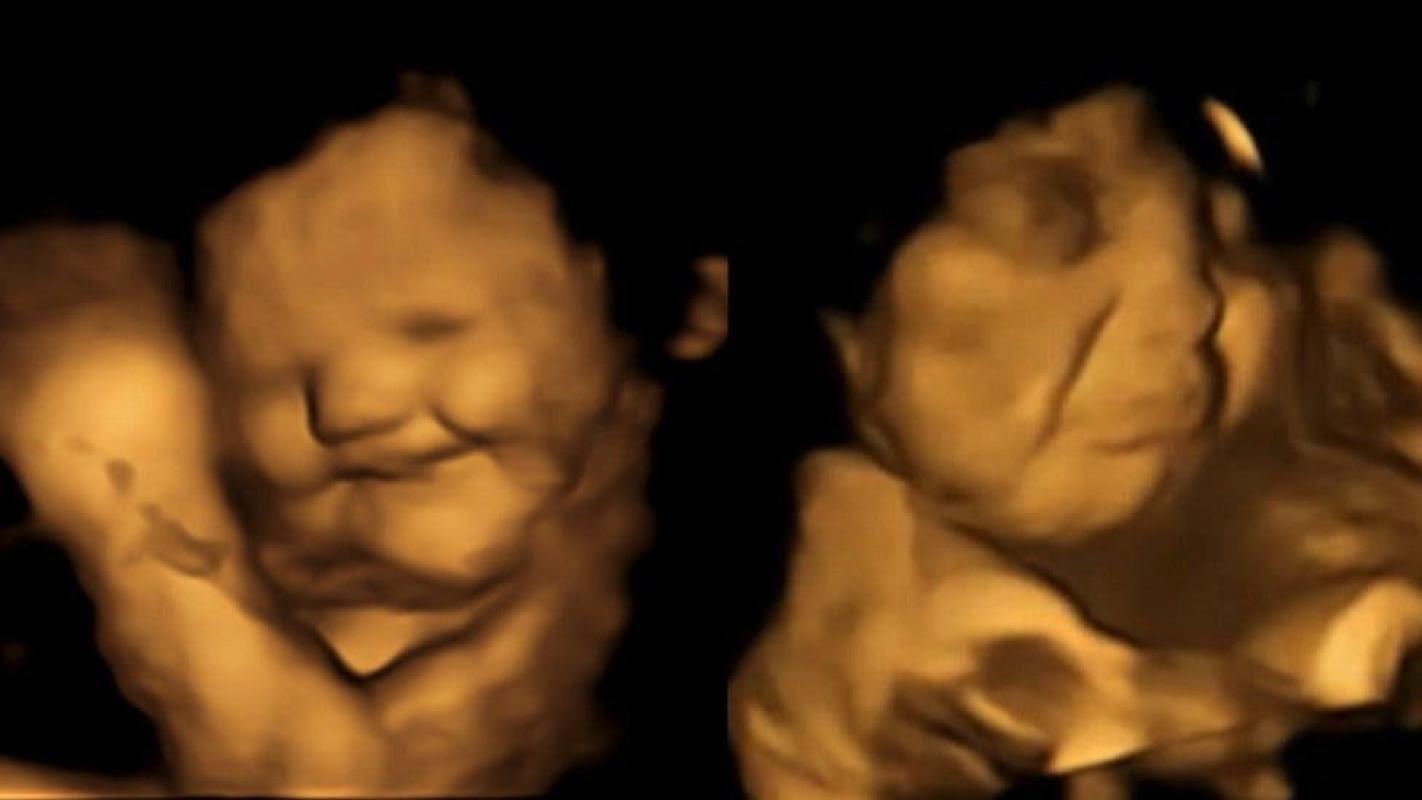

Si el sabor de la col rizada te hace fruncir el ceño, no estás sola. Los científicos han descubierto que los fetos en el útero parecen sonreír después de que sus madres comen zanahorias y fruncen el ceño después de que coman esa col.

En el estudio que publicaron en la revista Psychological Science, el grupo informó que 20 minutos después de que las madres tragaran las cápsulas las ecografías 4D mostraron que la mayoría de los fetos expuestos a la col parecían hacer una mueca.

Mientras tanto, los expuestos a las zanahorias parecían estar sonriendo.

El grupo de control de las 30 mujeres embarazadas que no comieron nada no tuvo las mismas respuestas.

Las muecas y sonrisas que se ven en los ultrasonidos "podrían ser solo movimientos musculares que reaccionan a un sabor amargo", dice Reissland, aunque agrega que es sabido que los fetos hacen expresiones faciales.

El doctor Daniel Robinson, profesor asociado de neonatología en la Facultad de Medicina Feinberg de la Universidad Northwestern, en Estados Unidos, quien no participó en la investigación, le dijo a la cadena NBC que las personas no deberían interpretar que las imágenes de ultrasonido muestran que los fetos expresan felicidad o desagrado.